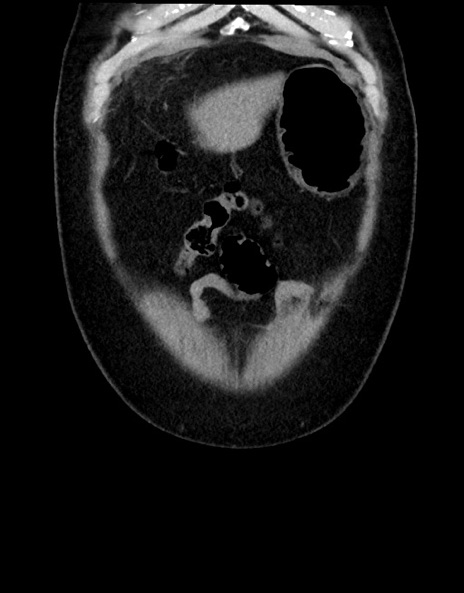

横断像

【症例】70歳代男性

【主訴】腹痛

【現病歴】今朝から腹痛あり。全体的に痛い。特に左上の方。排ガスが今日はない。冷や汗が出る。

【既往歴】直腸癌術後

【身体所見】左側腹部〜上腹部に圧痛あり。腹膜刺激症状明らかなではない。軽度反跳痛。左下腹部に術後瘢痕あり。

【データ】WBC 7700、CRP 0.02